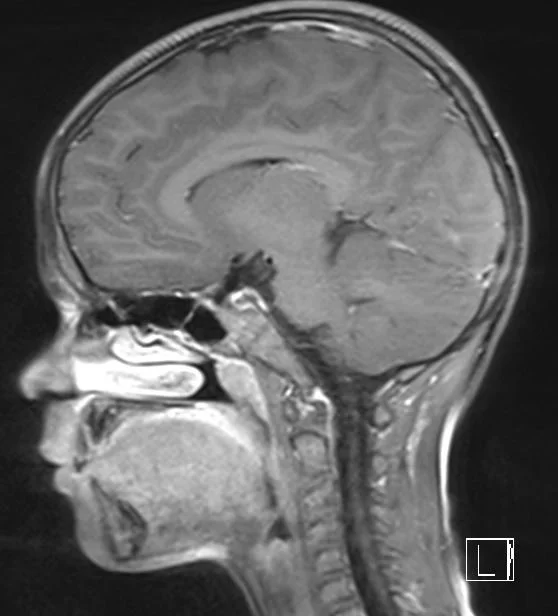

Rare and pediatric disease trials come with complex challenges that require specific expertise and experience. We have the radiology exerts to support the specific requirements of pediatric clinical trials. Many rare diseases affect children, and pediatric trials bring additional challenges.

They require specific protocols, involve additional regulations and demand expertise and experience. BICL’s experts are experienced in oncology, MSK and other pediatric disorders including growth plate disturbance, bone age and osteochondroma.